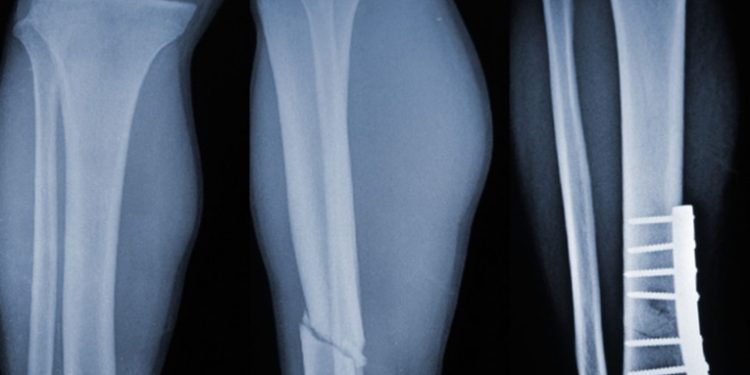

A diferencia de los métodos tradicionales, que requieren placas metálicas, clavos o tornillos, el Bone 02 utiliza una tecnología adhesiva inspirada en la naturaleza, particularmente en la capacidad de las ostras para adherirse de manera firme y estable a superficies húmedas y difíciles. Gracias a esto, la cirugía para reparar huesos se vuelve rápida, menos invasiva y con mejores resultados a largo plazo.

Según reportes oficiales, el pegamento posee una resistencia mecánica comparable a las placas de titanio, pero con la ventaja de que no requiere cirugías posteriores para retirar el material. Además, el adhesivo es biocompatible y se degrada de manera controlada a medida que el hueso recupera su integridad original.